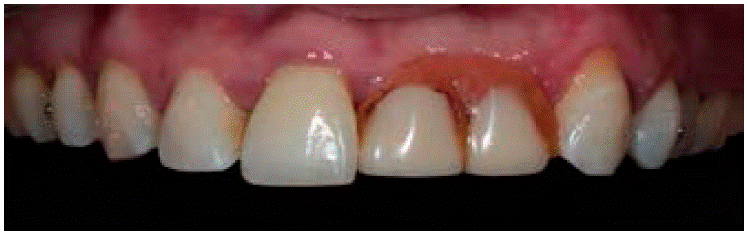

Se decidió retirar la prótesis parcial removible previa a la cirugía y se le colocó un provisional de los órganos dentales 13 al 23 para disminuir tiempos quirúrgicos, favorecer una adecuada higiene y mejorar el aspecto dental de la paciente (Figura 5).

La paciente acudió a consulta un mes después de la intervención quirúrgica. A la exploración intraoral se observaron tejidos blandos afrontados sin presencia de infección ni exposición de la lámina ósea y se retiraron puntos de sutura. La paciente no refirió molestias (Figuras 10AyB).